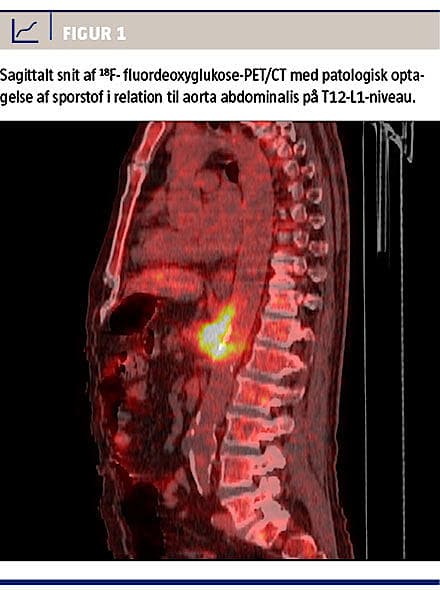

Bloddyrkninger viste vækst af S. dublin med samme resistensmønster som ved det tidligere tilfælde. Transøsofageal ekkokardiografi var uden

tegn til endokarditis, men 18F-fluordeoxyglukose (18F-FDG)-PET/CT (Figur 1) viste patologisk øget metabolisme i tæt relation til aorta abdominalis, og en CT af abdomen fem dage senere viste udvikling af et mykotisk aortaaneurisme på niveau med afgangen af truncus coeliacus.